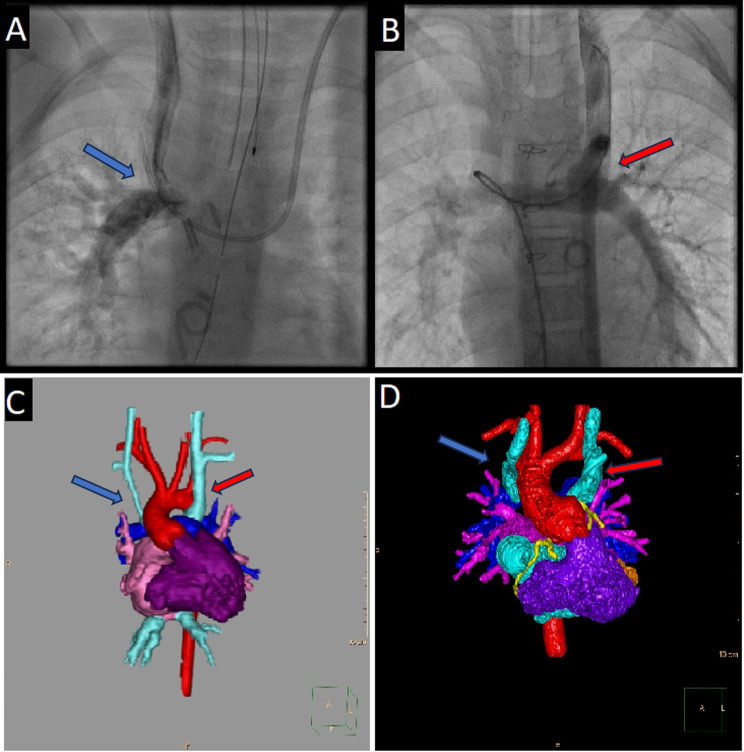

Abstract Image